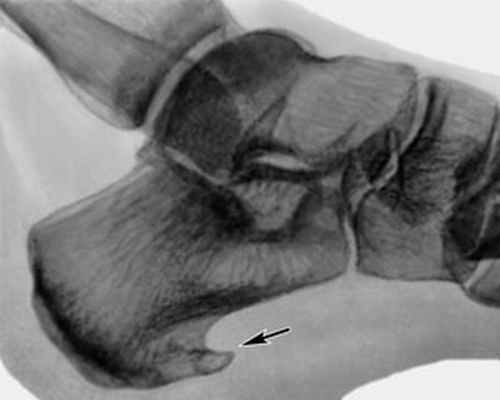

Уточнить диагноз позволяет рентгенография стопы. При этом на рентгенограмме виден костный нарост.

После консультации диагноз «пяточная шпора» подтвердился – на рентгеновском снимке костный нарост был четко виден. На приеме специалисты клиники объяснили женщине: методы, на которые она возлагала надежды, эффективны только в самом начале заболевания. А так как Наталье Борисовне пяточная шпора не один год мешает нормально жить, операция была единственным верным решением. Более того, медлить с вмешательством было ни в коем случае нельзя.

Ренген-снимок до операции Рентген стопы после операции

Диагностикой и лечением пяточной шпоры занимается врач ортопед. Основным способом выявить патологию и оценить степень ее развития является рентгенография. На снимке хорошо виден костный нарост, его форма, расположение и величина.

После изучения истории болезни, жалоб пациента, врач проводит осмотр ноги: наличие высокого свода, площадь болезненности в области пятки, наличие ограничений подвижности в стопе. Для верификации диагноза могут потребоваться инструментальные методы исследования. Рентгенография позволяет получить четкое изображение костных тканей. Это метод исследования дает возможность исключить другие причины болей в пятке,такие как перелом или артроз. Пяточная шпора хорошо визуализируется при рентгенографии.